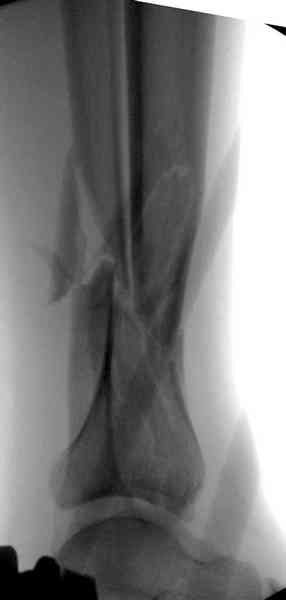

При высокоскоростных переломах редко можно встретить изолированную травму пилона, и в моей практике изолированные травмы большая редкость, поэтому, как дополнение к обсуждаемой теме, решил представить свежий, двухдневной давности случай.

Предыдущей сменой до 4:00 утра по поводу открытого перелома бедра, тибиал плато, пилон и надколенника сделана операция.

Пострадавшему 21 г., травма скоростная, после I&D с расширением раны, на бедре сделана операция ретроградным интрамедуллярным штифтом, остеосинтез с частичной резекцией надколенника и ушивание собственной связки.

На голень наружный фиксатор, рану на бедре ушили (рана была изнутри кнаружи всего 2 см). По протоколу травматических больных, до операции обследован ангиографически, (у больного дистально не смогли определить пульсацию) сосудистый хирург подтвердил проходимость на всем протяжении магистрального сосуда нижней конечности по снимкам ангиограмм.

КТ пилона имеем.